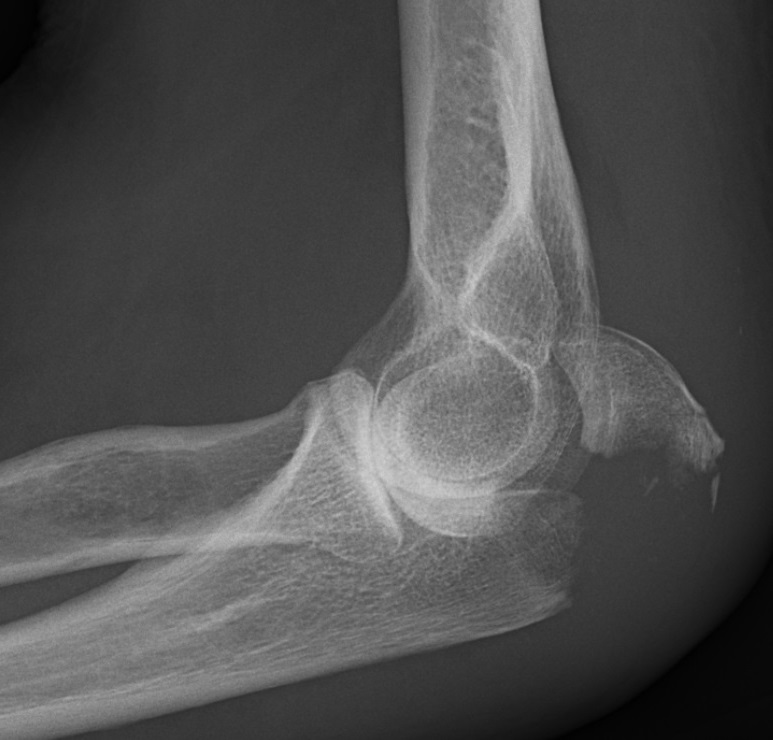

Exempel på olekranonfraktur Mayo 2A